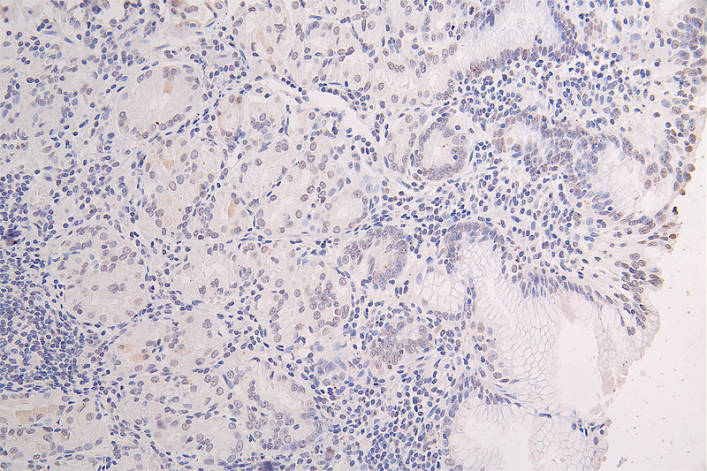

IHC image of CSB-RA943659A0HU diluted at 1:100 and staining in paraffin-embedded human gastric cancer performed on a Leica BondTM system. After dewaxing and hydration, antigen retrieval was mediated by high pressure in a citrate buffer (pH 6.0). Section was blocked with 10% normal goat serum 30min at RT. Then primary antibody (1% BSA) was incubated at 4°C overnight. The primary is detected by a Goat anti-rabbit polymer IgG labeled by HRP and visualized using 0.08% DAB.